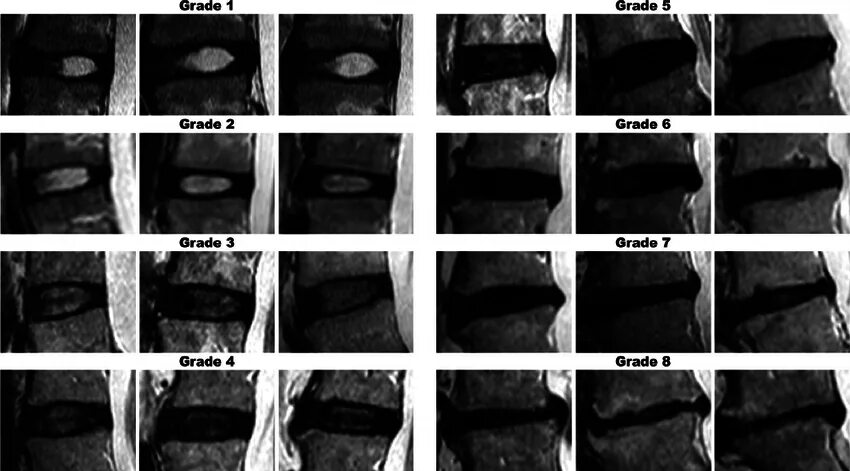

Дегенерация межпозвонкового диска по pfirrmann